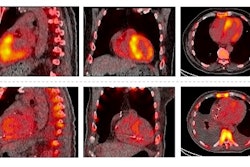

Typical transthyretin amyloidosis cardiomyopathy (ATTR), early detected ATTR, and a non-ATTR on cardiac MRI and SPECT/CT. Four-chamber cardiac MRI cine image (A), typical diffuse late gadolinium enhancement on cardiac MRI (B), and positive SPECT/CT (C) in a typical ATTR cardiomyopathy patient. The white outline denotes the whole left ventricular (LV) volume of interest (VOI) to obtain maximum myocardial standardized uptake value (SUVmax). Black and yellow circles demonstrate left and right atrial blood pool regions of interest. Four-chamber cardiac MRI cine image (D), nontypical septal predominant late gadolinium enhancement on cardiac MRI (E), and septal SPECT/CT uptake in a patient with early detected ATTR (white asterisk). The red arrow points to a minor right ventricular signal. Negative control patient on cardiac MRI (G and H) and SPECT/CT (I). The white line denotes the LV region of interest in SPECT/CT-negative patient. ECV = extracellular volume; LV MBR = left ventricular myocardium-to-blood ratio. Image and caption available for republishing under Creative Commons license (CC BY 4.0 DEED, Attribution 4.0 International) and courtesy of the Journal of Nuclear Cardiology.

According to the analysis, the LV MBR was higher in ATTR patients than non-ATTR patients (4.6 vs. 0.9, p < 0.001). Further, the group determined that an LV MBR greater than 1.5 was the optimal cut-off value to differentiate ATTR from non-ATTR patients with an accuracy of 100%.